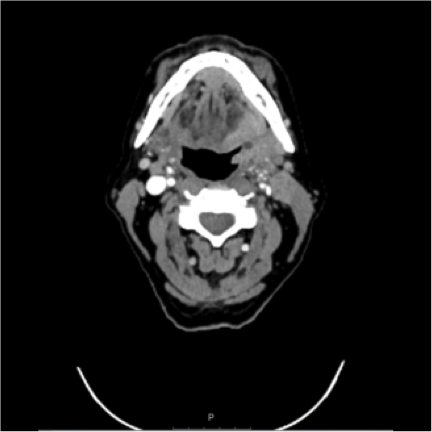

The clinical examination revealed an ulcerated and enlarged left tonsil and left cervical lymphadenopathy levels II and III. A Neck CT Scan with contrast medium revealed a mass on the left tonsil. A Thorax+Abdomen CT Scan with contrast medium revealed no metastasis. We performed a Panendoscopy and the pathologist described it as a squamous cell carcinoma (G2) with p-16 expression.